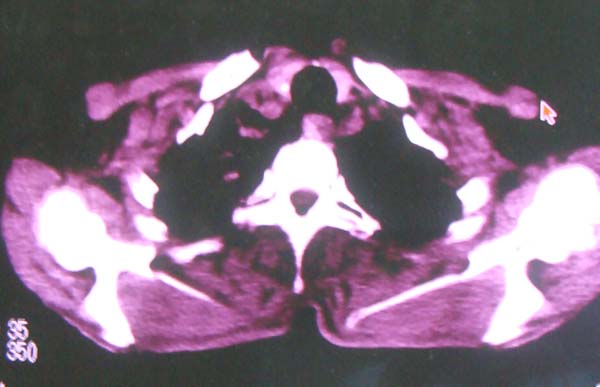

以下是引用zhangzhongshou在2008-2-15 22:25:00的发言:[br]片子照得不清,基本考虑1、细支气管肺泡癌2、亚急性血行播散型肺结核。请结合临床。片子细节显示不清,无法提供进一步意见。

以下是引用杀毒软件在2008-2-15 22:34:00的发言:[br]小叶中心性肺气肿。两肺弥漫性病变,肺泡微石病,过敏性肺炎,尘肺2期,特发性肺纤维化都有可能。[br]不象肺泡癌。